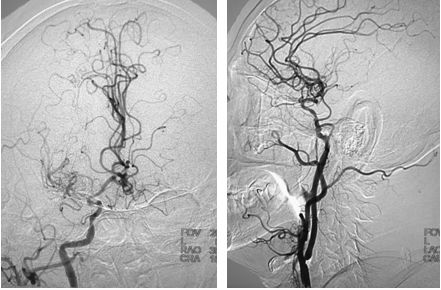

局麻下,将8F导引导管上行至颈总动脉远端,在路径途指导下,将微导丝(Transcend)、微导管(Echelon-10)通过颈内动脉狭窄段至C2段,造影证实微导管位于真腔内,颈内动脉末端闭塞,交换出微导管,沿导丝送入Maverick(2.0x20mm)球囊至狭窄处,予以扩张球囊,造影提示狭窄有所改善,导引导管上行困难,遂沿导丝送入Wallstent(9x30mm)支架至狭窄处,释放支架,造影提示残余狭窄率约为60%,遂沿导丝送入LitePAC (4.0x30mm)球囊至狭窄处予以后扩张,造影提示狭窄明显改善,将球囊半充盈状态,导引导管沿球囊越过支架支颈内动脉C1段远端,再次造影示颈内动脉末端仍然闭塞,(图6)

图6

在路径途指导下,将微导丝(Transcend)、微导管(Rebar 027)沿导引导管送至左侧大脑中动脉M2段,撤出微导丝,经微导管造影,造影证实微导管位于真腔内,大脑中动脉远端血管通畅,将取栓支架Solitaire AB (6x30mm) 送至血栓处,释放取栓支架,静置5分钟后取出支架,可见支架内大量血栓,复查造影提示左侧大脑前动脉、左侧大脑中动下干通畅,左侧前大脑前动脉可向左侧大脑中动脉代偿供血,(图7)此时患者右侧肢体无力症状明显好转,仍有不完全混合性失语,观察10分钟后复查造影提示血流仍然通畅,颈动脉支架处血流通畅,遂结束手术,继予以替罗非班抗栓治疗。

图7